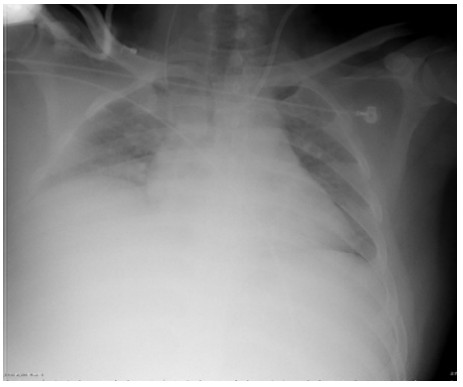

SAP发生呼吸衰竭的原因很复杂,其原因有以下几种。(1)SAP因为炎症反应导致的ARDS(图 1),这是普遍认为的一种原因,但实际上ARDS在SAP患者呼吸衰竭中很多时候是非主要原因。SAP急性期虽然病情进展很快,出现多脏器功能损伤,甚至休克,有类似于脓毒症和感染性休克样的表现,但其炎症反应并不如脓毒症这么强烈,大量的研究可见SAP发生过程其IL-6很少过千,而脓毒症则IL-6动辄大于5 000或10 000,SAP两肺影像学也很少有典型的非心源性肺水肿的双侧阴影,超声下也很少有“B线”表现。但胆道感染引起的脓毒症合并SAP的患者,其ARDS发生率会明显上升。现在随着高脂血症胰腺炎的增加,部分患者到院时同时存在糖代谢障碍,合并有糖尿病酮症,入院前后出现糖尿病酮症昏迷,有些患者会伴有呕吐误吸或者插管时误吸,这类患者在急性期会出现误吸相关的ARDS。(2)SAP是腹腔重症的一种,急性期因为腹膜后急性胰周液体积聚和急性胰周坏死物积聚,导致腹腔压力进行性升高,随之出现横膈抬高,两肺压缩,从而导致“小肺”,这和ARDS的“baby lung(小肺)”不同(图 1: ARDS;图 2、3: 腹内压14 mmHg和23 mmHg的对比,明显看到图 3呈现横膈抬高引起的小肺)。因横膈位置上抬导致小肺是SAP呼吸衰竭的主要原因。(3)两下肺不张(图 4)和胸腔积液(图 5):这两个原因也是导致SAP呼吸衰竭的主要原因,因为膈下刺激,导致两下肺的不张和大量胸腔积液常见于SAP患者,这两种原因导致的呼吸衰竭也和ARDS不同。(4)其他原因:胸腔出血、肺梗死和气胸亦可见于SAP相关呼吸衰竭,但相对少见。

| 图 2 腹内压14 mmHg |

| 图 3 腹内压23 mmHg |